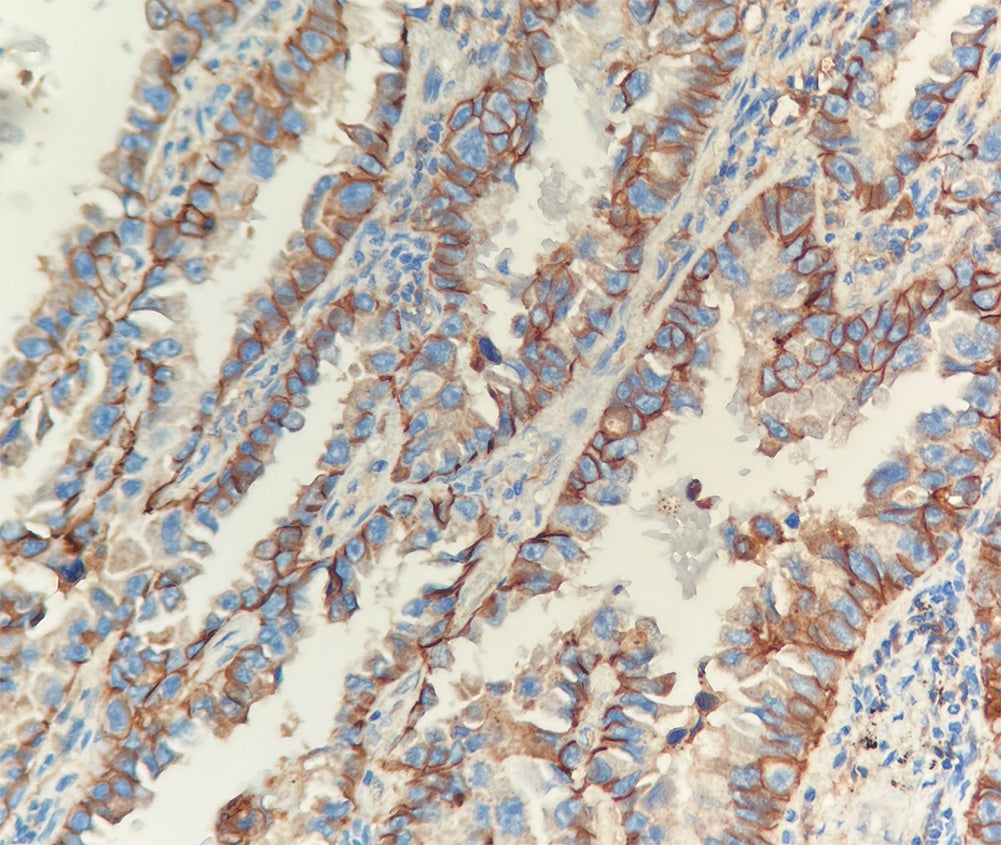

Cadherine épithéliale

Localisation : Membrane cellulaire

L’E-cadherine est positivement exprimée dans les épithéliums glandulaires et dans les adénocarcinomes pulmonaires, gastro-intestinaux et ovariens. Ce marqueur est utilisé pour différencier les adénocarcinomes des mésothéliomes et est également positif dans certains carcinomes thyroïdiens.

Contrôle positif : Tissu de cancer du sein